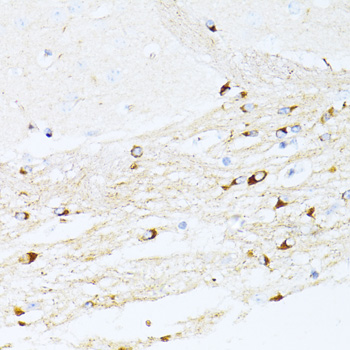

Immunohistochemistry of paraffin-embedded mouse brain using P21 at dilution of 1:100 (40x lens).